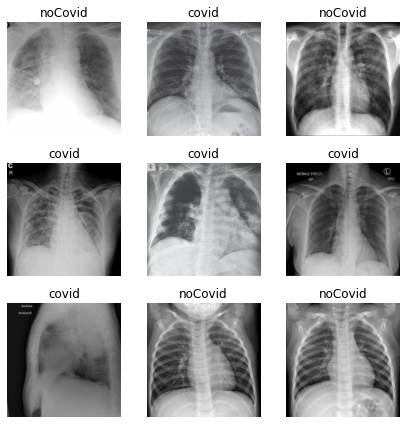

Pdf Deteccion Del Covid 19 Con Tecnicas De Deep Learning

Deteccion De Covid 19 En Imagenes De Rayos X Con Keras Tensorflow Y Deep Learning By Datacampero Medium

Detector De Covid 19 Usando Imagenes De Rayos X By Christian Tutiven Galvez Saturdays Ai Medium